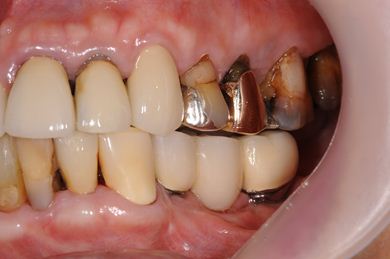

抜歯即日スピードインプラント治療+インプラント除去+セラミック治療

| 性別/年齢 | 女性 / 76歳 | ||||||||||||||||||||||||||||||||

| 主訴 | 20年前に入れたインプラントの周囲が腫れて気になっている。左下の一部治療後の歯が欠けている。 | ||||||||||||||||||||||||||||||||

| 治療内容 | インプラント5本(抜歯即日スピードインプラント)、ハイブリッドセラミック9本(セラミック用土台2本)、メタルボンドセラミック2本(メタルボンド用土台1本)、インプラント除去1本 | ||||||||||||||||||||||||||||||||

| 総治療費 | 2,514,645円 | ||||||||||||||||||||||||||||||||

| 治療期間 | 1年11ヶ月 |